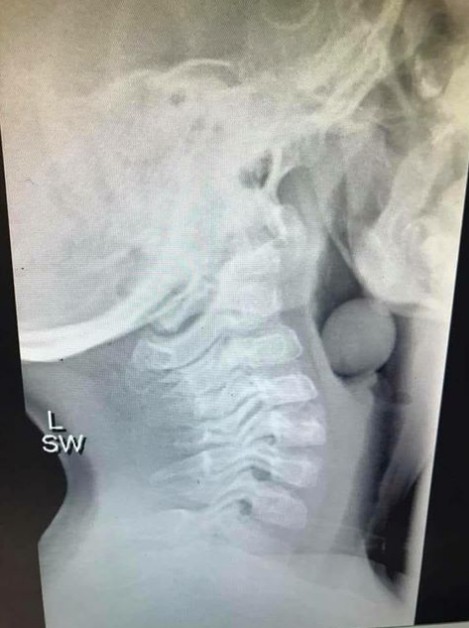

Questa lastra mostra come un chicco d'uva non tagliato può ostruire le vie respiratorie dei più piccoli

La foto in questione è un'immagine a raggi X che mostra chiaramente il chicco d'uva rimasto incastrato nella gola del figlio di 5 anni; fortunatamente le vie respiratorie non erano state del tutto ostruite, e ciò ha permesso al bimbo di sottoporsi ad un intervento per rimuovere l'ostruzione, salvandosi.